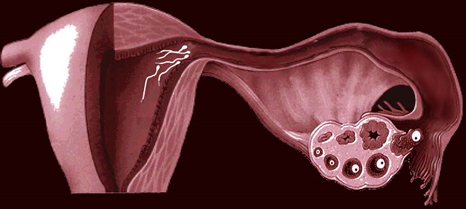

Органические поражения маточных труб — это непроходимость, или окклюзия маточных труб (рис. 1). Чаще всего причиной непроходимости являются спайки, которые могут образовываться как внутри маточных труб в различных ее отделах, так и вокруг труб, а также между фимбриями как результат воспаления.

Рис. 1. Непроходимость маточной трубы

Воспаление маточных труб может возникнуть в результате инфекционных заболеваний, передающихся половым путем, например, хламидиоза, гонореи и др., а также в результате абортов, послеродовых осложнений, аппендицита, перитонита. Причиной формирования спаек может быть и эндометриоз, о котором мы расскажем ниже.